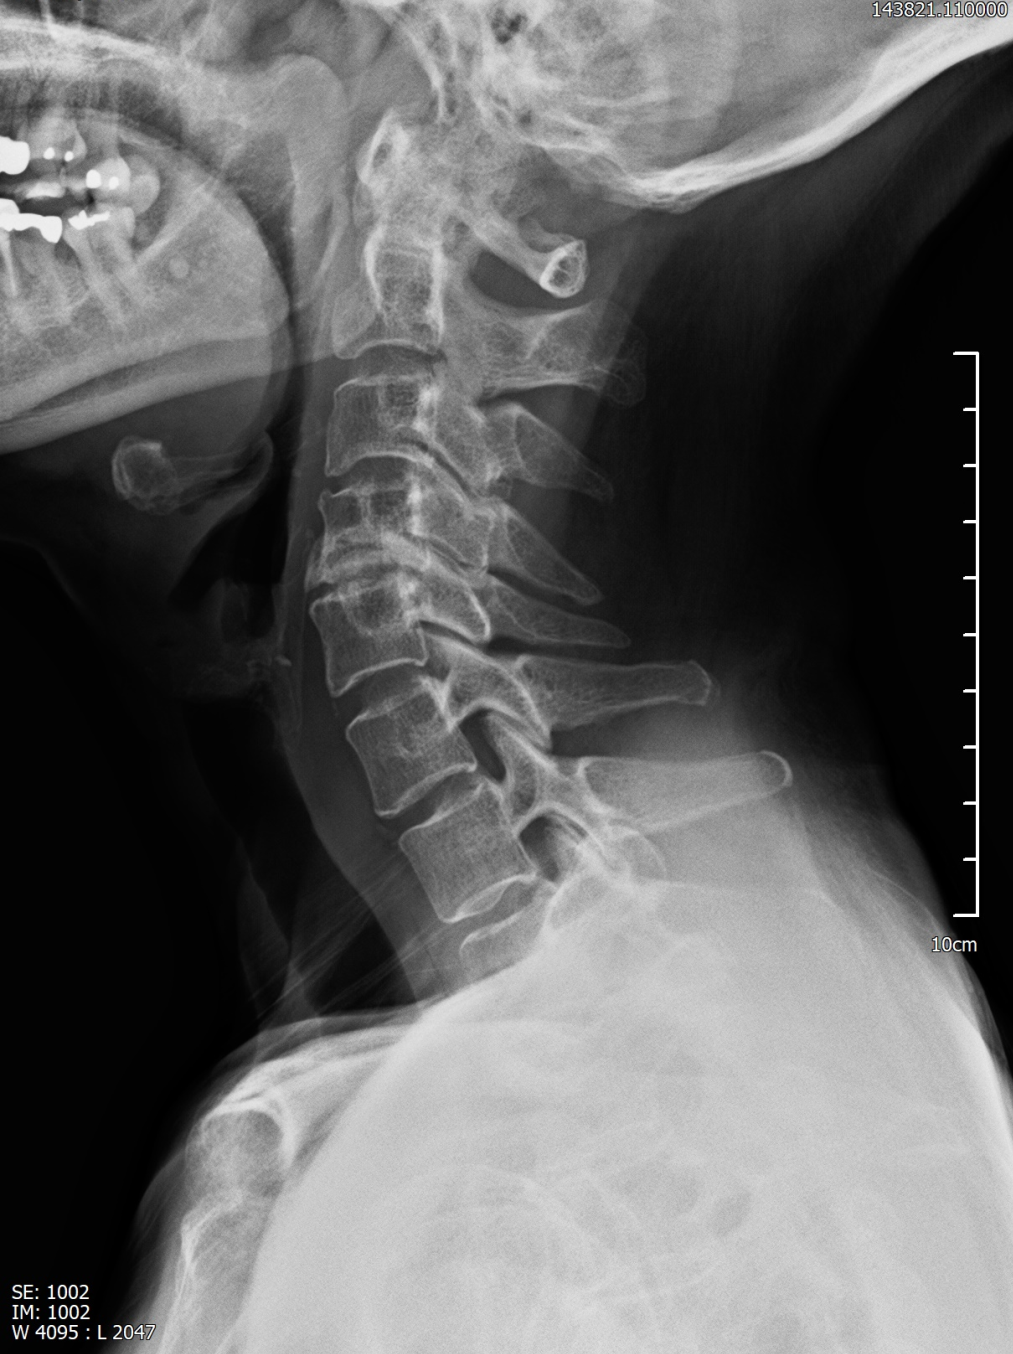

69세 여성 환자분께서 오복만세치과에 내원하셨습니다.

환자분께서는

왼쪽 귀 앞과 귀 안쪽이 아픈 느낌이 있고, 입을 크게 벌릴 때 아프고, 씹을 때도 통증이 있다고 하셨습니다.

실제로 턱관절은

입을 벌리고 다무는 과정에서 관절과 주변 근육, 인대, 디스크가 함께 작용하기 때문에

통증이 오래 가면 구조적인 문제를 먼저 떠올리게 됩니다.